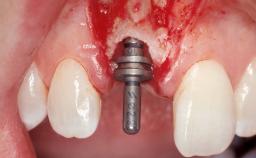

A 39-year-old male patient presented with a chief complaint of discomfort and gingival discoloration around his maxillary left central incisor. He was in good general health and was a non-smoker. His past dental history was significant because of the traumatic fracture of tooth 21 in a sporting accident at age 13. Initial dental treatment included endodontic therapy and a full-coverage restoration. The patient became symptomatic 5 years later, when structural failure of the tooth resulted in the dislodgment of the crown. Endodontic retreatment, apical surgery, and post-and-core restoration were performed.

Type of Implants One-Piece

Placement Protocol Early or late implant placement

Bone Volume Deficient horizontally, requiring prior grafting